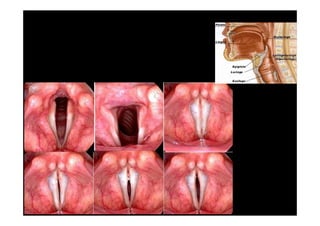

• LARINGE

LARINGE – PREGAS VOCAIS